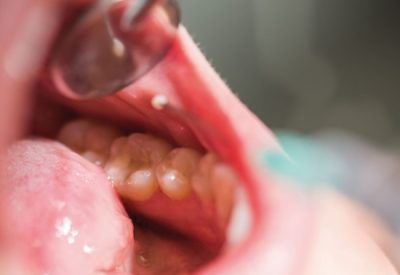

Oral cancer is a type of cancer that affects the mouth and surrounding areas, such as the cheeks, palate, lips, throat and jaw bones. It is important to be regularly checked by a qualified dentist in Kuala Lumpur when you…

Oral cancer refers to tumors that arise in the tissues of the mouth, including the lips, tongue, cheeks, floor of the mouth, and hard and soft palate. These tumors can range from benign (non-cancerous) to malignant (cancerous) and require treatment…